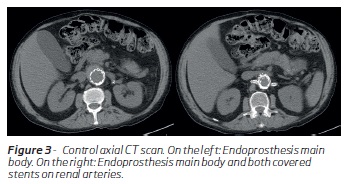

Before discharge, the patient had a control CT scan where no evidence of endoleaks were detected. (Figure 3,4 and 5)